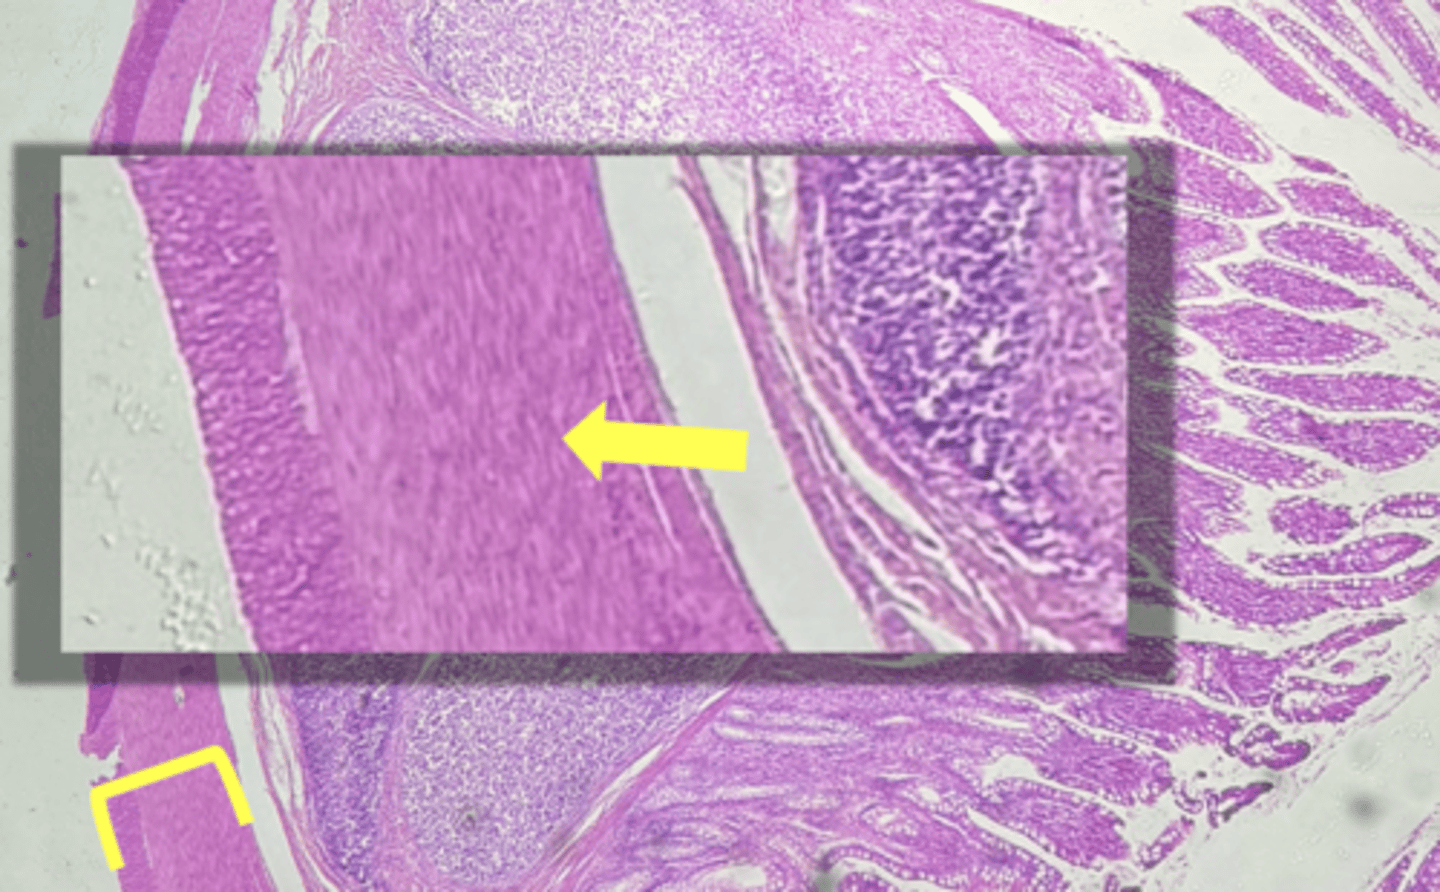

Esophagus

name the tissue

muscularis externa

(esophagus)

stratified squamous epithilium (KEY CHARACTERISTIC)

circular layer

longitudinal layer